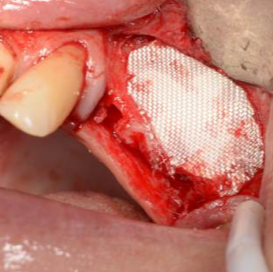

- Schließen des Osteotomiefensters zum Sinuslift

- Wundversorgung nach Entnahme von Weichgewebstransplantaten

- Sicherung der Schneider-Membran, auch als Perforationsversorgung